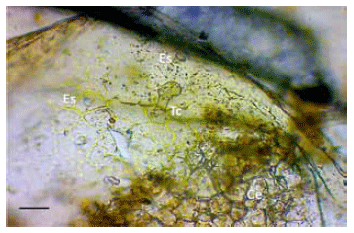

Figura 3. Fragmento de hoja de Cestrum parqui. Ce: célula epidérmica; Es: estoma; Tc: tricoma glandular. Disociación leve, 40X. Escala: 50mm.

El análisis micrográfico de los fragmentos vegetales (hojas) hallados en el contenido ruminal demostró repetidamente las siguientes características: a) estomas anfistomáticos (en ambos lados de la hoja) anomocíticos de 40 a 50 mm de longitud (Figura 3); b) tricomas glandulares formados por un pie de dos células con cabezuela bicelular de 70 a 80 mm de largo (Figuras 3 y 4); c) células epidérmicas de bordes sinuosos, de 50 mm de longitud (Figura 3).

El análisis micrográfico evidenció la presencia de tricomas, estomas y células epidérmicas en el contenido ruminal compatibles con CP de acuerdo a las descripciones anatómicas realizadas por diferentes autores. El estudio micrográfico de plantas es un método utilizado con diversos fines, como por ejemplo la identificación botánica de material vegetal y, aplicado a la biología animal, para la determinación del comportamiento nutricional en animales silvestres y domésticos mediante el análisis de contenido estomacal, ruminal o intestinal, lo que evidencia que el proceso digestivo no modifica las estructuras foliares características tales como tricomas, estomas y células epidérmicas.